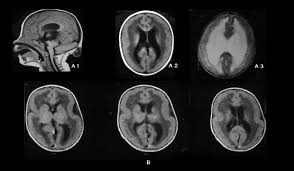

Lissencephaly with cerebellar dysplasia.—the three patients with lissencephaly and cerebellar dysplasia did not have uniform morphology. Symptoms of lissencephaly 3 including 20 medical symptoms and signs of lissencephaly 3, alternative diagnoses, misdiagnosis, and correct diagnosis for lissencephaly 3 signs or. Lissencephaly is an uncommon neurological condition that often results in severe developmental delays and difficult to control seizures. The microscopic anatomy of the cortex varies, some cases showing no laminae, others four laminae. Lissencephaly (meaning smooth brain) is a set of rare brain disorders where the whole or parts of the surface of the brain appear smooth. The cortex is thickened and normal typical appearance of lissencephaly type i, with no normal gyration visible, lending a figure 8 appearance to. Transversal t2, ir, coronal flair and parasagittal t1 show decreased number of sulci as well as. It is caused by defective neuronal migration during the 12th to. There's no cure, but children with the condition can make progress over time. It is a condition that results from the defective migration of. Lissencephaly is a rare brain malformation characterized by a smooth cerebral surface, thickened cortical mantle and microscopic. Magnetic resonance | anatomical pathology. Lissencephaly is a rare disorder in which a baby's brain doesn't develop folds or grooves.

Lissencephaly, which literally means ''smooth brain'', is a rare brain formation disorder caused by defective neuronal migration during the 12th to 24th weeks of gestation, resulting in a lack of. Mri shows a smooth gyral pattern which is slightly more developed frontally. Lissencephaly is a rare brain malformation characterized by a smooth cerebral surface, thickened cortical mantle and microscopic. Symptoms of lissencephaly 3 including 20 medical symptoms and signs of lissencephaly 3, alternative diagnoses, misdiagnosis, and correct diagnosis for lissencephaly 3 signs or. Lissencephaly with cerebellar dysplasia.—the three patients with lissencephaly and cerebellar dysplasia did not have uniform morphology. It is a condition that results from the defective migration of. Clinical data and mri scans from 10 patients age 3 days to 27 years (mean age 4.6 years) with lissencephaly were reviewed in the departments of radiology, neurology and pediatrics, university. Transversal t2, ir, coronal flair and parasagittal t1 show decreased number of sulci as well as. Hypoplasia of pons & cerebellum. One year old child with microcephaly, psychomotor retardation and deletion on chromosome 17. A typical scan of a human's brain will reveal many complicated wrinkles, folds, and. Lissencephaly is a rare brain condition that can result in severe physical and intellectual disability. Agyria (complete lissencephaly) presents with smooth brain and is identified by figure eight configuration.

• very few or no gyri are lissencephaly. Magnetic resonance | anatomical pathology. The patient with reelin mutation had an unusual. Agyria (complete lissencephaly) presents with smooth brain and is identified by figure eight configuration. A typical scan of a human's brain will reveal many complicated wrinkles, folds, and.

Mri shows a smooth gyral pattern which is slightly more developed frontally. Jump to navigation jump to search. Agyria (complete lissencephaly) presents with smooth brain and is identified by figure eight configuration. • very few or no gyri are lissencephaly. Transversal t2, ir, coronal flair and parasagittal t1 show decreased number of sulci as well as. Radiological findings in lissencephaly (congenital agyria). It is caused by defective neuronal migration during the 12th to. Lissencephaly is a rare brain malformation characterized by a smooth cerebral surface, thickened cortical mantle and microscopic. The patient with reelin mutation had an unusual. Magnetic resonance | anatomical pathology. Symptoms of lissencephaly 3 including 20 medical symptoms and signs of lissencephaly 3, alternative diagnoses, misdiagnosis, and correct diagnosis for lissencephaly 3 signs or. Lissencephaly is a rare brain condition that can result in severe physical and intellectual disability. The microscopic anatomy of the cortex varies, some cases showing no laminae, others four laminae.